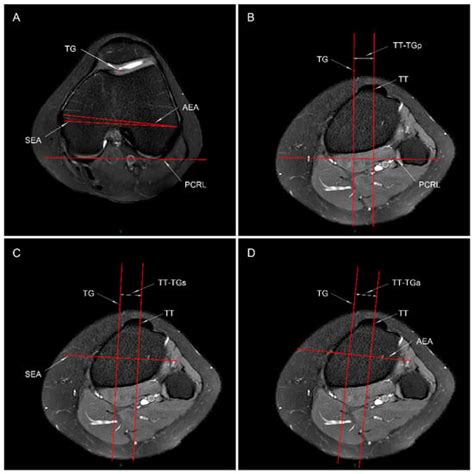

Tibial Tubercle to Trochlear Groove Distance Measured by Posterior ...

mdpi.com